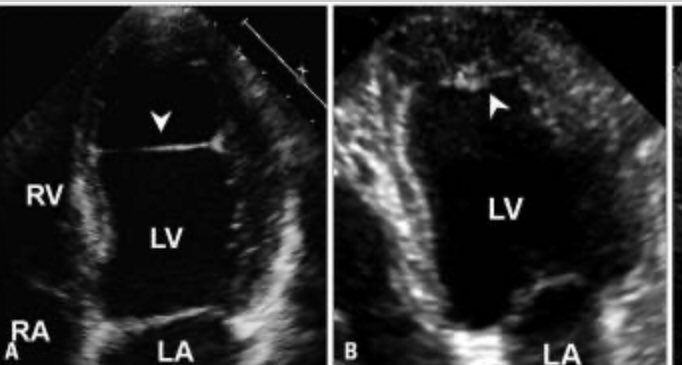

What are your pearls for assessing the mechanism & severity of #mitralregurgitation by #EchoFirst?...

What are your pearls for assessing the mechanism & severity of #mitralregurgitation by #EchoFirst? #JACCIMG presents an imaging-based curriculum to review functional #mitralvalve...